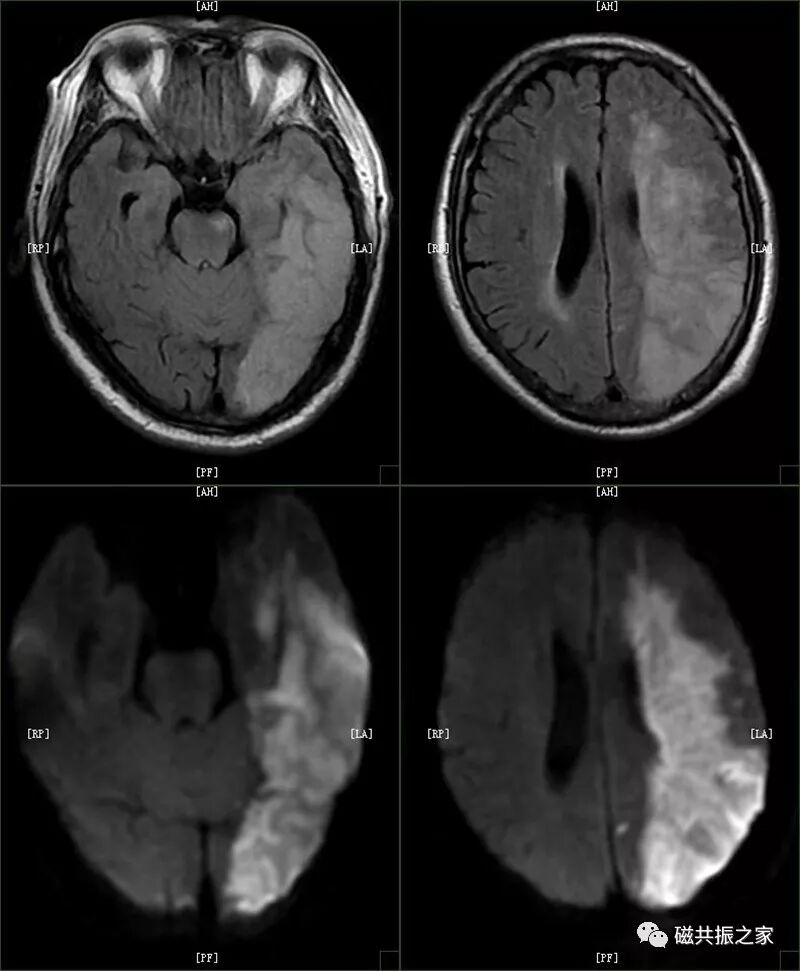

2.中枢神经系统:脑内(脑干)出血,出血量大于 30ml;蛛网膜下腔出血急性期;大范围脑挫裂伤;急性大面积脑梗死,颅内大动脉瘤,动脉瘤破裂。

D:-CT-MR室资料新闻稿文件夹微信图片_20211127090802.jpg脑干出血

图片D:-CT-MR室资料新闻稿文件夹微信图片_20211127090807.jpg大面积脑梗死

D:-CT-MR室资料新闻稿文件夹微信图片_20211127090812.jpg颅内血肿